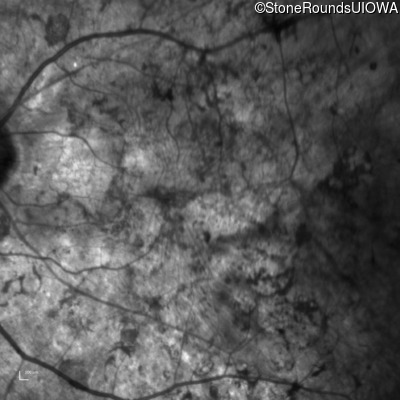

Infrared Fundus Photograph - Right - Hand Motion sc

Exemplar